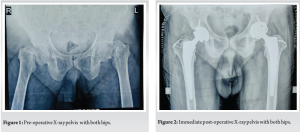

It is exceedingly rare for a patient to sustain non-traumatic fractures of bilateral femoral neck. While hip fractures are commonplace injuries treated by orthopedic surgeons, they characteristically occur unilaterally in elderly individuals with osteoporosis resulting from trival trauma such as a fall or a high-energy trauma in young individual. Bilateral femoral neck fractures, on the other hand, represent an infrequent clinical presentation often linked to contributing factors such as metabolic diseases or chronic renal disease that compromise bone integrity, the physiologic stress following electroconvulsive therapy procedures, or violent muscle contractions during a seizure episode as documented across the medical literature [1,2]. Of particular singularity are cases where these highly uncommon bilateral fractures arise in the acute aftermath of an epileptic seizure – only a very limited number of such instances have been reported worldwide to date. Fig. 1.

We present a case of a 68-year-old gentleman, a known epileptic for the past 15 years. Following a significant epileptic episode, he encountered abrupt and intense pain in both hip joints while in bed during the night. Subsequent to the episode, he found himself unable to mobilize or elevate his legs. A subsequent examination by his family physician the following morning prompted a portable X-ray, which suggested bilateral femoral neck fractures. The patient, under consistent anti-epileptic therapy (Tab Eptoin-Phenytoin and Tab Levera-Levetiracetam) for the past 15 years, had been seizure-free for the preceding 12 years. Approximately 3 months before the incident, a neuro-physician, assessing his condition, conducted an EEG with normal results, recommending a discontinuation of medication. On general examination, evidence of a tongue bite indicated a seizure during sleep. Although his MRI brain exhibited age-related atrophy without significant pathology, he was referred to our orthopedic department for further management. At the time of presentation, the patient was conscious, cooperative, and well orientation, with both limbs in adduction and external rotation. He experienced tenderness in the groin and significant pain on movement of both the hips, with no neurological or vascular deficits. Pelvic AP radiographs revealed Garden type IV transcervical neck of femur fractures with comminuted greater trochanter fractures in both hips. Despite having no previous hip pain and an active lifestyle, maintaining full functionality with weight-bearing. The severe displacement of hip fractures, delayed presentation, combined with his age and quality of bone, led us to anticipate a failure of osteosynthesis. Consequently, we planned bilateral total hip replacement surgery. Following thorough counseling with the patient and his family, staged bilateral hip replacement surgeries were proposed. Femur canal was Dorr B type, and pre-operative templating and planning led to the selection of uncemented prostheses (although cemented implants were kept backup) with a Ceramic on Poly bearing [3]. Comminuted fractures of the greater trochanter on both sides were addressed using two Tension band wires and non-absorbable supplementary Ethibond no. 5 sutures. The surgical procedure involved an anterolateral approach, utilizing a 32mm diameter head for the Pinnacle Poly constrained acetabular liner with a 50 mm outer shell diameter (DePuy, Warsaw, IN, USA) and a size 15 Corail cementless stem in the left hip. Subsequently, after a 5-day interval, the right hip underwent a similar procedure with similar implants. Both intraoperative and post-operative periods transpired without complications. Fig 2.